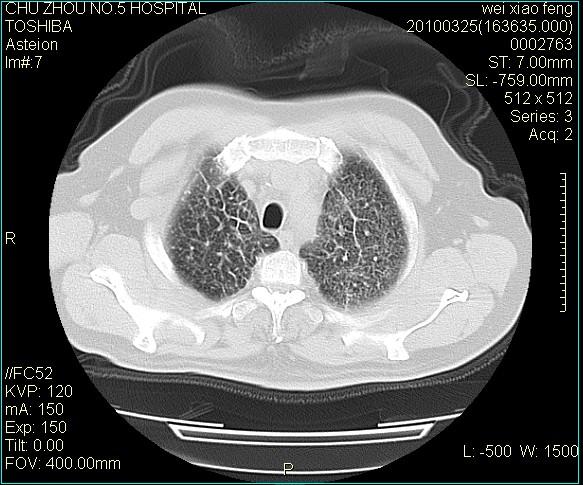

男,60岁,反复咳、痰、喘3月,加重3天。

双肺间质性改变。

考虑双肺血型潘散肺结核/

间质性肺炎伴间质纤维化!不排除伴有职业病!

双肺间质纤维化,双肺血型潘散肺结核。

考虑间质性肺炎伴间质纤维化。

间质病变,间质炎症,间质纤维化趋势

间质性肺炎